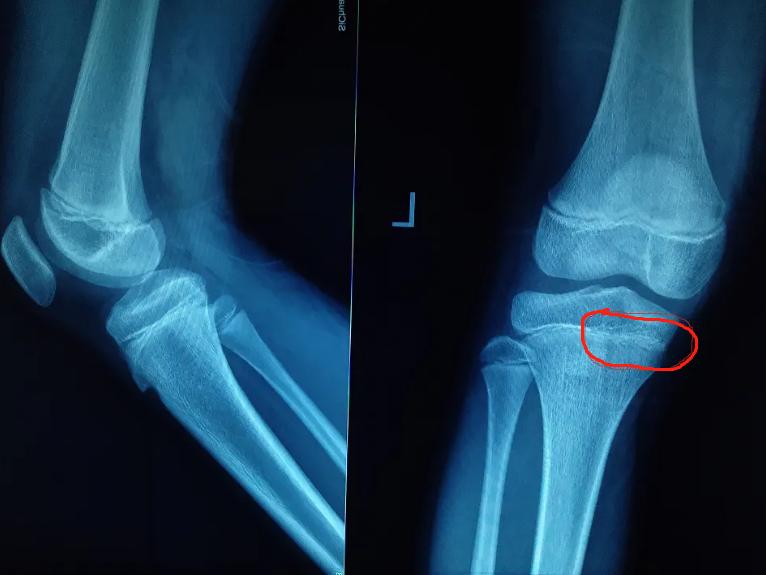

常见原因3:生长板老化

这类孩子也常见,一般出现在大骨龄孩子身上,比如女孩接近14岁骨龄、男孩接近15岁骨龄,这时候生长板逐渐失去活力、钙化,分裂的能力已经大幅度下降了,所以会出现长得慢、长不高的情况。

对于生长板老化的孩子,可以采用中医或西医的方法延缓骨龄,给孩子多争取几个月甚至一年半载的,能多长一点是一点,不能放任不管,尤其是身高本身就不高的孩子。